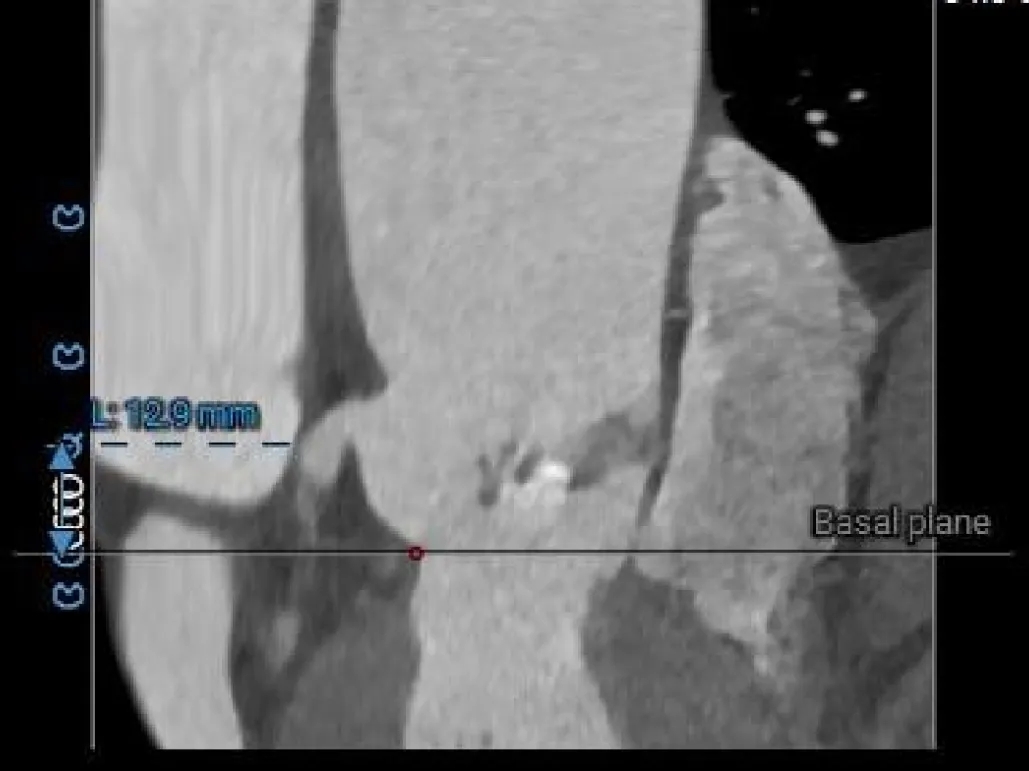

冠脉风险评估

LCA Height

RCA Height

LCA & Leaflet

RCA & Leaflet